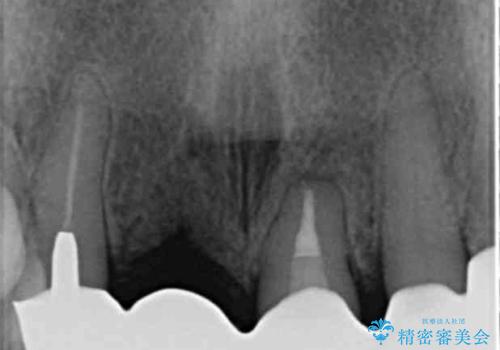

根尖病変の存在が判明したため、感染根管治療後にオールセラミックジルコニアクラウンを製作します。